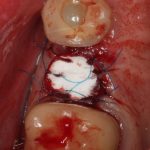

Кстати, обрати внимание на ширину альвеолярного гребня (левая картинка). Она чуть меньше 3 мм. Это объясняет, почему я засомневался в возможности установки имплантатов одновременно с остеопластикой. Понятно и без КЛКТ.

Возвращаемся к основной операционной области. Еще раз посмотрим на альвеолярный гребень, поофигеваем от его ширины и моих грандиозных планов:

Я зафиксировал костный блок практически без адаптации на несколько винтов. Обрати внимание, что винты находятся в зоне, где не планируется установка имплантатов. Фиксация должна быть надежной, поскольку мне еще предстояла подготовка лунок для имплантатов. Трех винтов для этого вполне достаточно.

Глянем на то, что получилось: